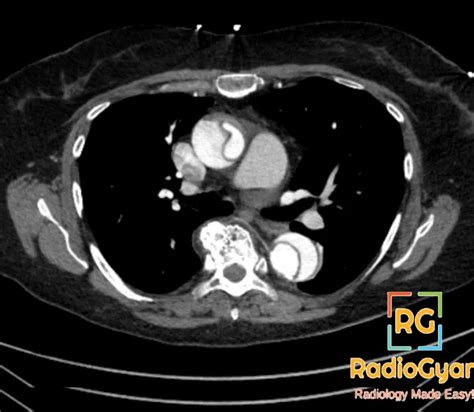

Aortic Dissection CT Features that Distinguish True Lumen from False Lumen | AJR

Understand the critical role of Aortic Dissection CT scans in life-saving diagnosis. This guide explains how rapid computed tomography imaging identifies this medical emergency, the diagnostic accuracy of contrast-enhanced protocols, and why timely CTA interpretation is essential for managing acute aortic syndrome. Learn the imaging standards used by radiologists to detect thoracic dissections and ensure prompt, life-saving clinical intervention.